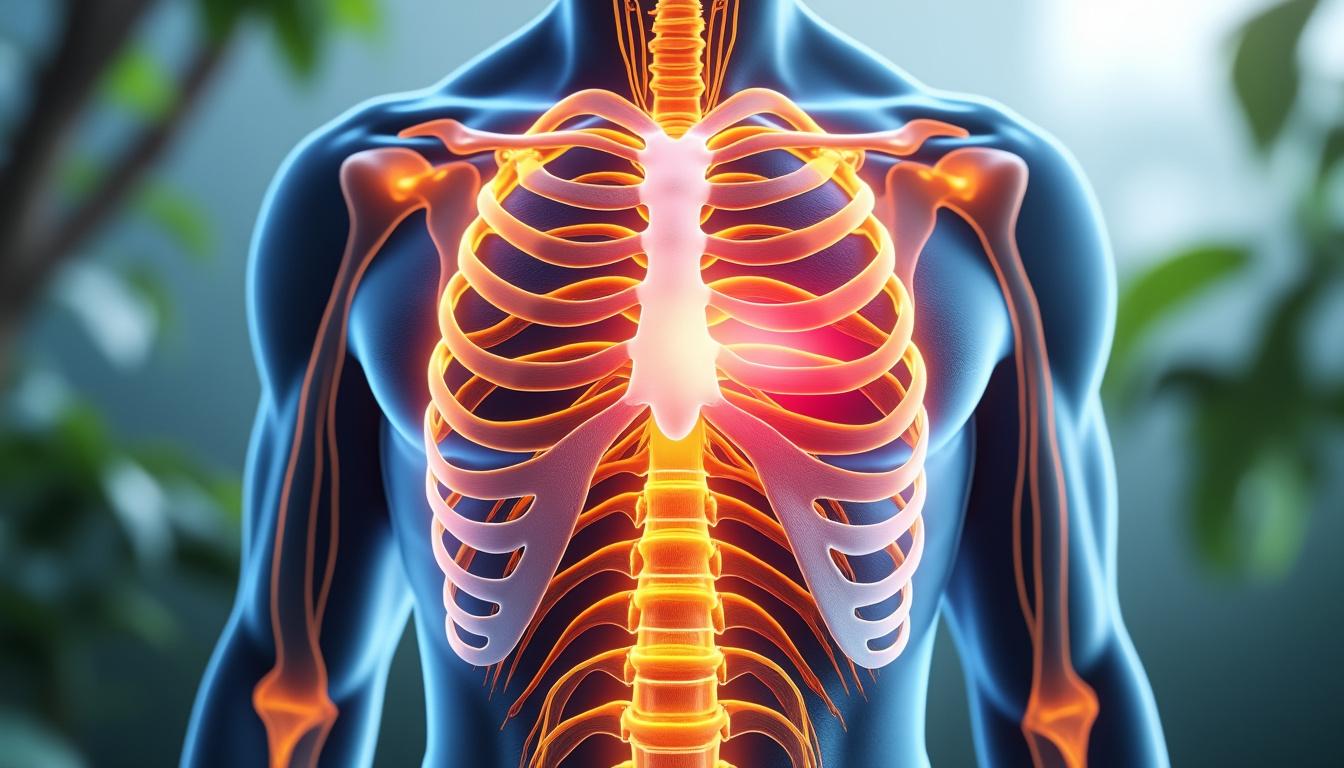

Impossible d’ignorer ce petit picotement ou cet élancement entre deux côtes. La douleur intercostale se manifeste de différentes manières selon la personne, le moment, le contexte émotionnel voire même… le simple hasard d’un mouvement mal coordonné ! Le thorax, avec son architecture musculaire complexe et ses nerfs sensibles, reste un carrefour où se croisent tensions du quotidien, émotions, respirations forcées et parfois, séquelles d’anciens chocs.

Une douleur intercostale se décrit souvent comme un tiraillement, une brûlure ou parfois une sensation de « coup de poignard ». Elle s’intensifie généralement lors d’un inspir profond, à la toux ou lorsqu’on adopte une position inhabituelle. Chez certains, elle demeure localisée à un seul point côté gauche ou droit ; pour d’autres, elle rayonne sur le thorax ou s’accompagne d’une gêne à la respiration.

La multiplicité des causes impose d’écouter attentivement ses sensations, de ne pas minorer une douleur qui s’aggrave ou persiste, et d’observer les signaux qui pourraient orienter vers une consultation médicale. Cette vigilance, alliée à une attitude posée, favorise une gestion harmonieuse et rassurée de son bien-être thoracique. Mieux comprendre le fonctionnement de cette région, c’est déjà avancer sur le chemin de la guérison.